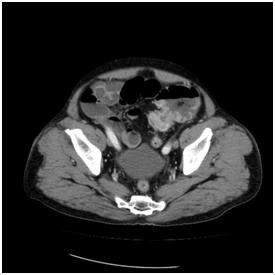

대장암으로 장폐쇄가 생겨서 유발된 변비 대장암으로 장폐쇄가 생겨서 유발된 변비

[서울대병원 제공]